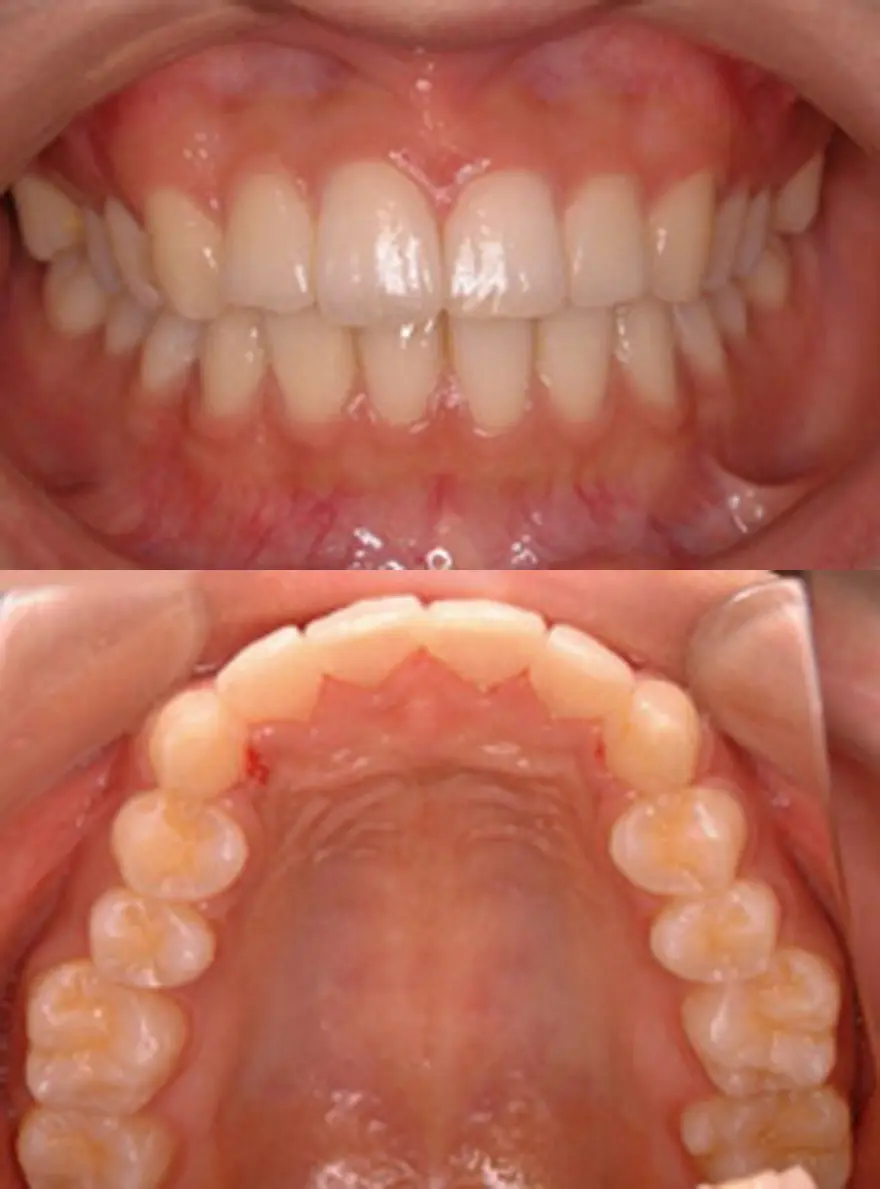

MTM(部分的な矯正)治療例4

矮小歯のあるケース

| 患者さまの年齢・性別 | 20代・男性 |

| 治療期間 | 5ヵ月 |

| 治療費(税込) | 242,000円 |

| 主訴 | 前歯の隙間が気になる。 |

| 診断名・主な症状 | 真ん中のスペースの閉鎖と右の矮小歯が裏側になってしまっている。 |

| 治療に用いた主な装置 | セルフライゲーションブラケット装置(デイモンシステム) |

| 治療内容 | 前歯の隙間を閉じ、右の裏側にある歯を前方に移動させています。上顎左右の前歯の隣の歯が矮小歯と言う本来より小さい歯のため、このままでは再度隙間があいてくる可能性があります。矯正治療後、この歯を少し大きくする治療が必要となります。 |

| 抜歯部位 | 非抜歯 |

| 通院回数・メンテナンス頻度 | 5回 |